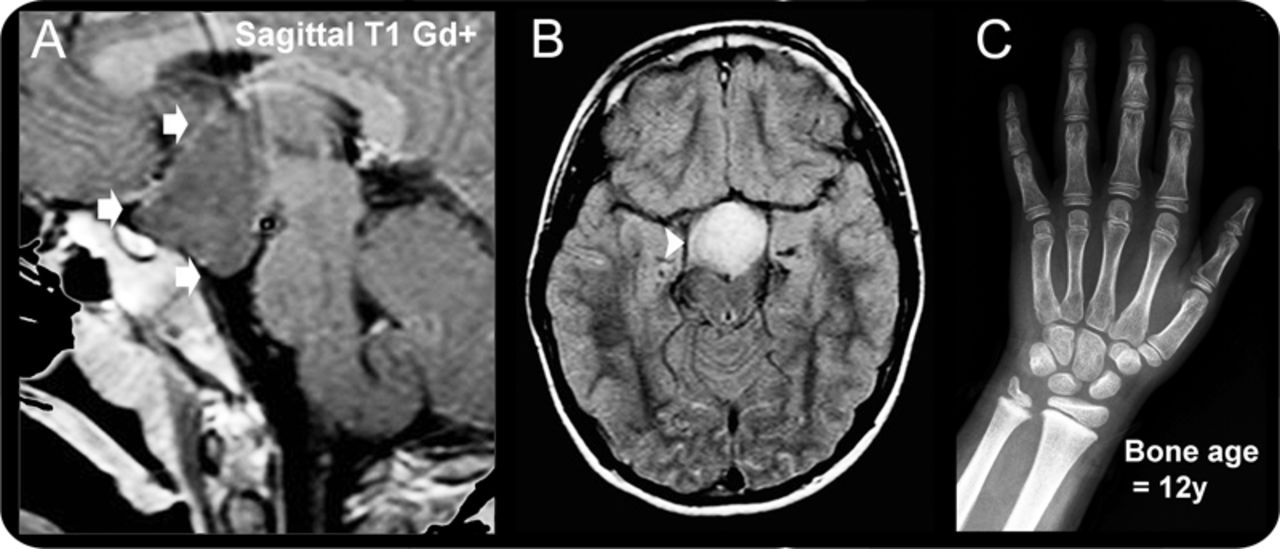

(A, B) MRI证实nonenhancing HH(箭头)。典型的hyperintensity fluid-attenuated反转恢复(箭头)。(C)先进的骨龄。

孤立HH hyperintense在fluid-attenuated反转恢复并导致性早熟(PP)当他们面向向下(parahypothalamic病变),癫痫占主导地位在固着intrahypothalamic HH。2小灵通与isointense灰质HH,多指趾畸形,皮肤的并指,裂成两半的会厌,肛门闭锁,panhypopituitarism,激活造成移码突变(映射到染色体7 p13)作为一个常染色体显性遗传特点。1

所有的答案,我们收到了来自个人居民而非团体和他们都合理周到。三个被调查者正确识别的经典外观孤立下丘脑错构瘤(图1)和Pallister-Hall综合症(图2)。孤立时,下丘脑错构瘤呈现严重癫痫、更重要的神经功能障碍,更有可能与性早熟。Pallister-Hall综合症患者通常有控制癫痫发作和内分泌干扰性早熟。

教学这个神秘案件,尽管类似外观的MRI定位和T2 / fluid-attenuated反转恢复特征可能有助于区分这两个实体,因此成像可以作为临床预后因子的进化。